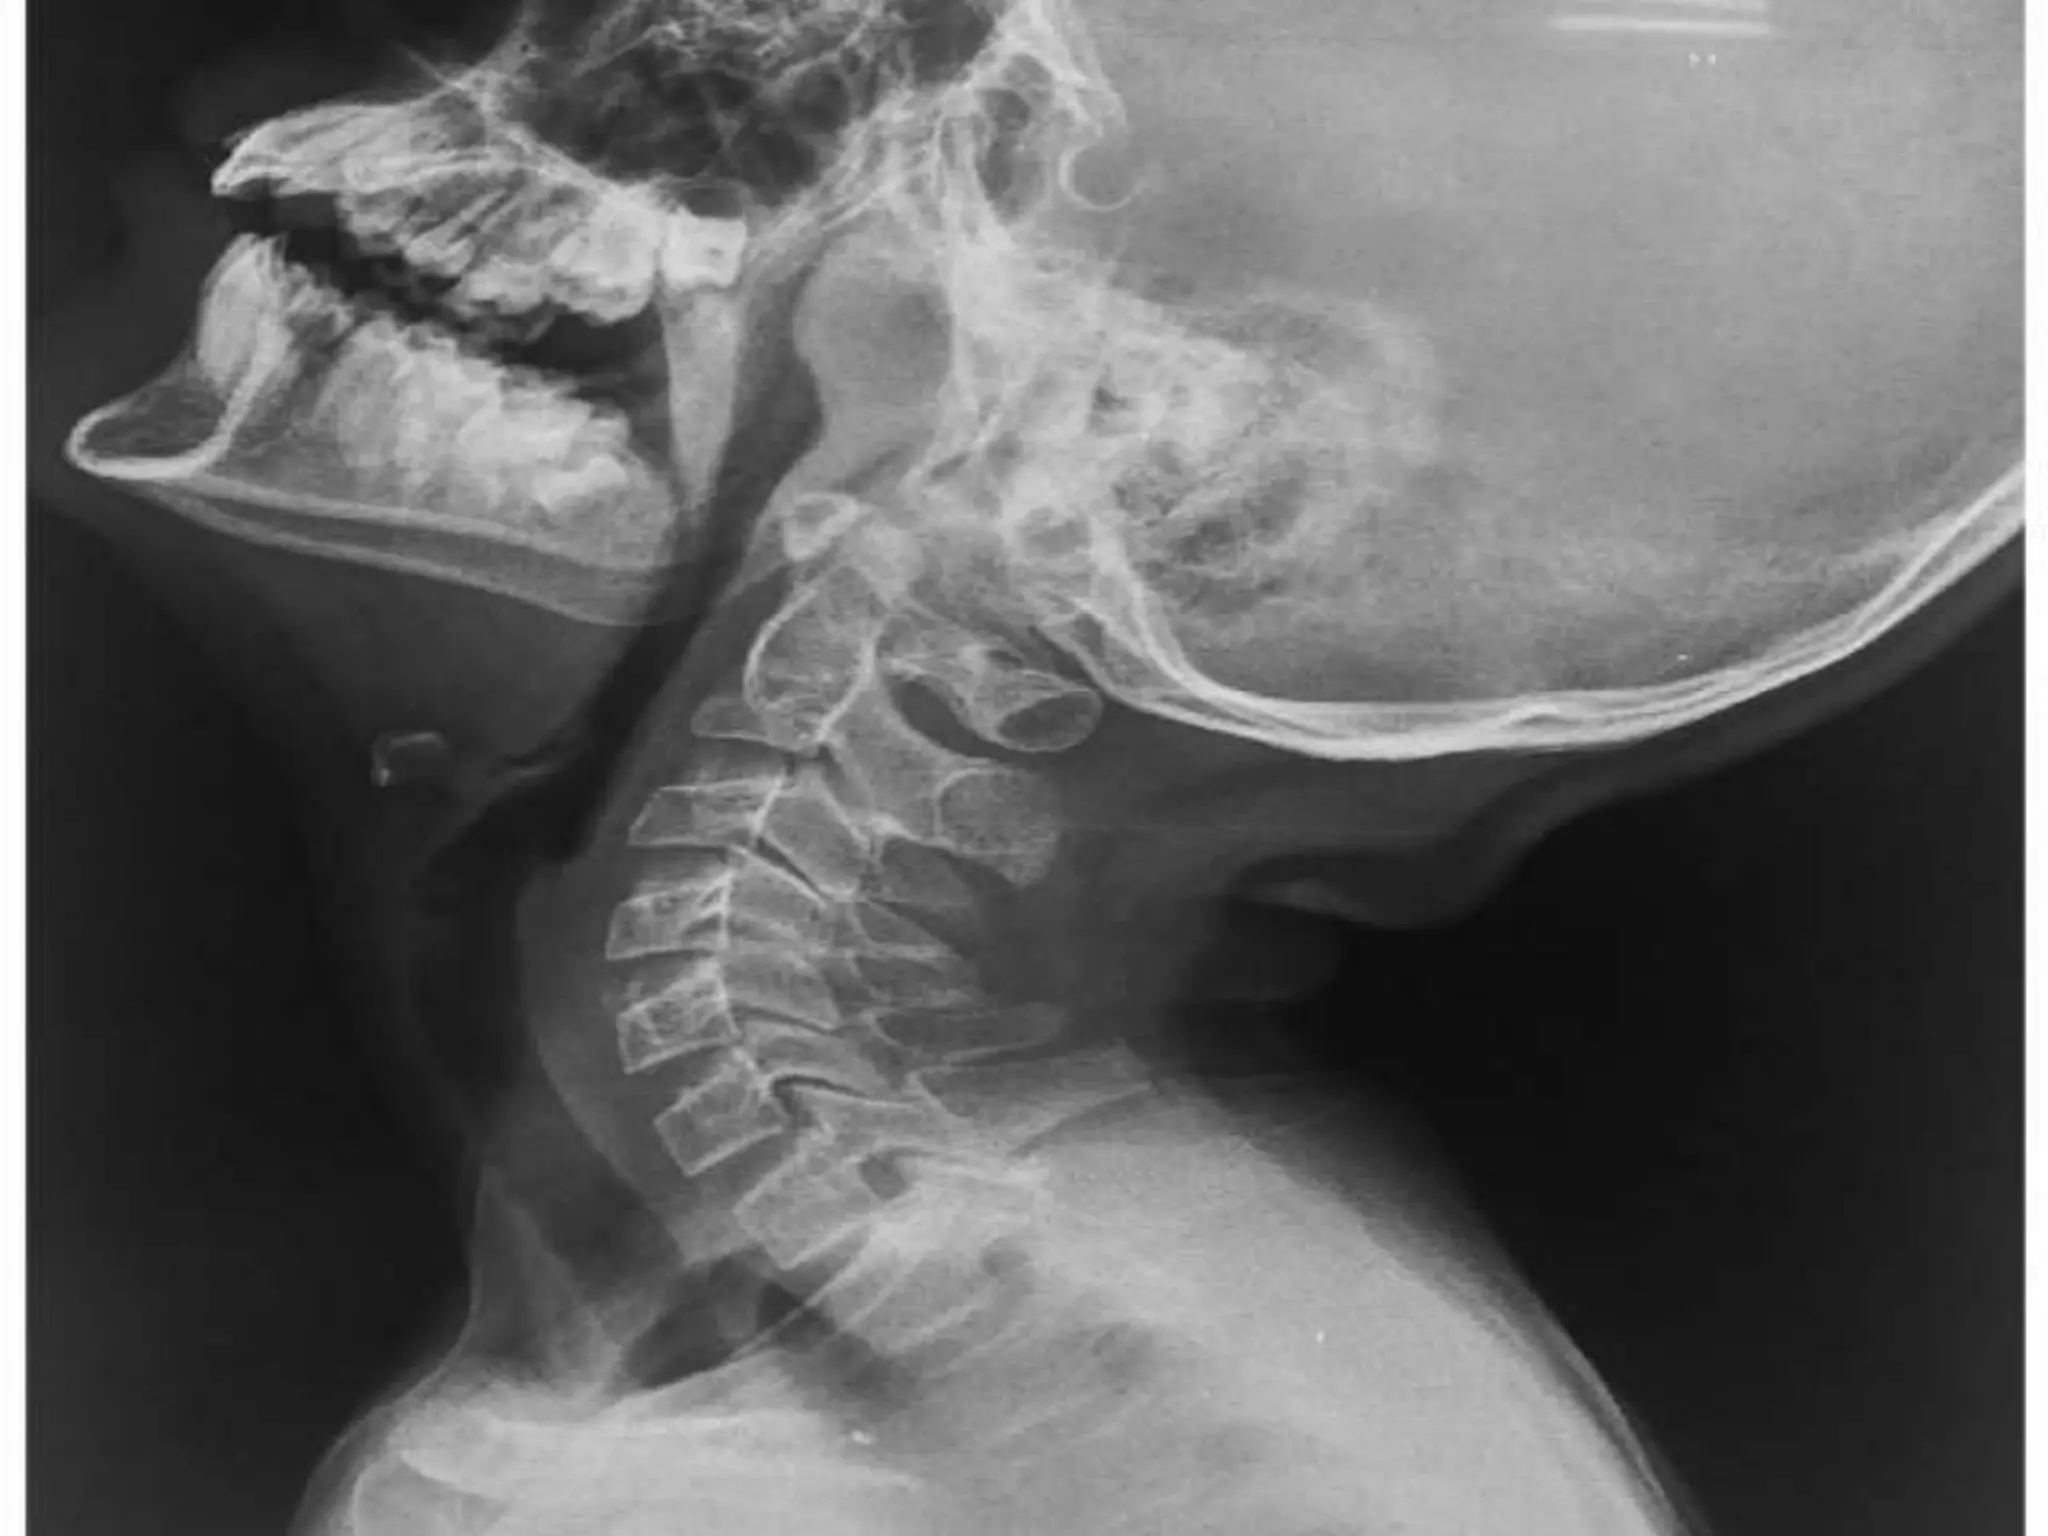

What are adenoids? Adenoid Hypertrophy, Clinical features and